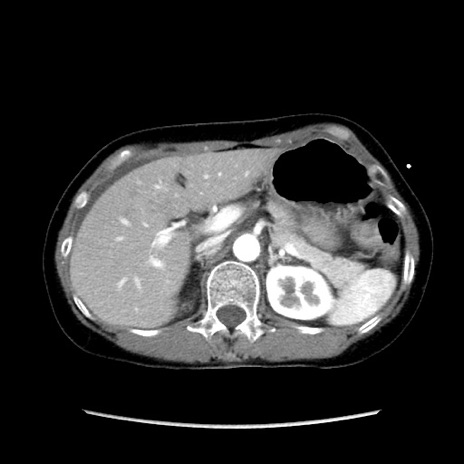

矢状断像

【症例】40歳代 女性

【主訴】上腹部痛、嘔気・嘔吐

【現病歴】約9時間前頃から急に上腹部痛、嘔気、嘔吐が出現。改善しないため救急要請。

【既往歴】子宮頚癌(広汎子宮全摘術、放射線療法)、腸閉塞

【身体所見】腹部:平坦、軟、腸雑音亢進、上腹部を中心に腹部全体に圧痛あり。

【データ】WBC 8400、CRP 0.03